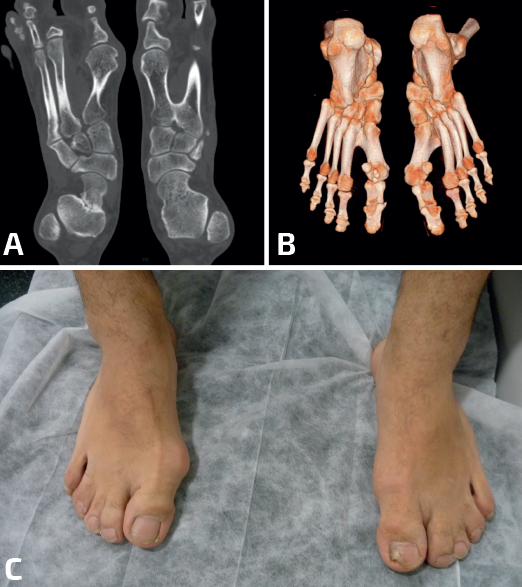

- Talonavicular: la mayoría de las coaliciones talonaviculares son congénitas, con herencia autosómica dominante, pero en algunos casos pueden formarse durante la preadolescencia(16). En el estudio radiológico es característico el “signo de la seta”, visible en las radiografías en carga en proyección dorsoplantar, donde los contornos de la fusión ósea remedan la forma de un hongo(14)(Figura 2). Es frecuente la existencia de este tipo de coalición en síndromes malformativos como el de Nievergelt-Pearlman(17). Cuando una coalición talonavicular es sintomática, suele serlo de manera leve, con molestia más que dolor(18,19,20,21,22). En la mayoría de los casos el tratamiento conservador suele ser suficiente para mejorar la sintomatología(23,24). Cuando es necesaria una cirugía, suele realizarse una corrección de la deformidad con una osteotomía(25).

- Calcaneocuboidea: las coaliciones calcaneocuboideas suelen encontrarse en combinación con otras coaliciones (Frost y Pensieri) y también en el contexto de cuadros sindrómicos como el de Crouzon(26,27,28). Revisando nuestra casuística de coaliciones, los autores encontraron un caso de una paciente no sindrómica con una coalición aislada calcaneocuboidea bilateral que cursó con un pie plano valgo muy sintomático. La cirugía, consistente en una osteotomía varizante de calcáneo, mejoró la deformidad en valgo y la clínica hasta conseguir que la paciente estuviera asintomática (Figura 3).

- Naviculocuneana: revisando la literatura, llama la atención el alto número de coaliciones naviculocuneanas (navicular y primera cuña) recogidas en algunas series(29,30,31,32,33,34). Algunas radiografías en estos estudios nos recuerdan a artrosis primarias de esta articulación. El tamaño de las indentaciones articulares y de los quistes subcondrales parecen relacionarse directamente con la sintomatología(35). El tratamiento quirúrgico de las coaliciones naviculocuneanas, en un número bajo de casos, muestra resultados controvertidos. Algunos autores abogan por la resección simple con o sin interposición de partes blandas con buenos resultados(31) y otros recomiendan el tratamiento conservador por no obtener buenos resultados, independientemente de si se opta por una resección o por una artrodesis(29).

- Naviculocuboidea: en la literatura se encuentran publicaciones de casos aislados(36). La coalición naviculocuboidea no bloquea o afecta la mecánica de la subtalar ni del resto de las articulaciones vecinas, lo que explicaría que en la mayoría de las ocasiones son oligosintomáticas o asintomáticas. En escasas ocasiones el paciente se queja de dolor en la zona tras esfuerzos prolongados(37). Cuando son sintomáticas, es habitual que exista una deformidad en plano-valgo. El tratamiento conservador con plantillas suele resolver la mayoría de los casos(38). En los raros casos de sintomatología limitante a pesar del tratamiento conservador, la cirugía consistiría en la resección de la coalición y la interposición de músculo extensor brevis digitorum (pedio)(39,40). Las coaliciones naviculocuboideas se comportan, en la clínica y en la respuesta al tratamiento, de manera similar a las coaliciones calcaneonaviculares(41).